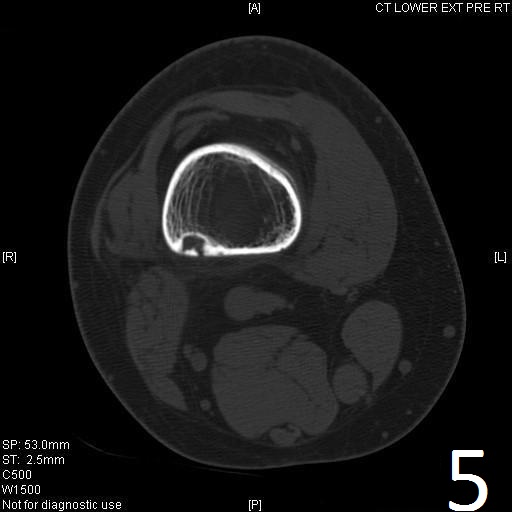

• Fibrous Cortical Defect: Small lesion (up to 1cm) that involves only the cortex (Fig. 5-7)

CT

• Useful for determining the true extent of the lesion

• Demonstrates well defined sclerotic borders

• Demonstrates expansile nature and scalloping of bone

• Useful for demonstrating internal trabeculations

Fig. 4-5: Sagittal (Fig. 4) and axial (Fig. 5) CT reconstruction of the lower extremity shows a well circumscribed, small sclerotic cortical lesion consistent with a fibrous cortical defect.